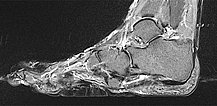

Auch in der nativen, T1-gewichteten MRT sagittal ohne Kontrastmittel (gleiche Schnittebene) ist der Bindegewebsnävus homogen hypointens (schwarz).